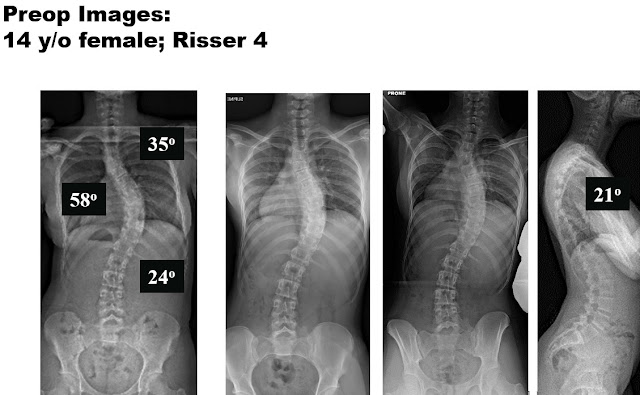

The case example is a 14 year old young lady with a 58 degree right thoracic idiopathic curve, and 35 degree proximal thoracic and 24 degree lumbar curves.

The supine side bending radiographs demonstrate the flexibility of the spine. So only the main thoracic curve of 58 degrees is what we call “structural” and the other two curves, due to the fact they bend out to be below 25 degrees, we call “nonstructural” or “compensatory”.